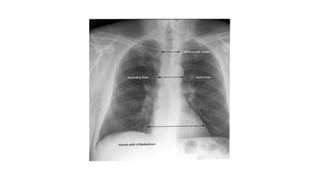

Mediastinum

• The trachea should be centrally located or slightly to the right

• The aortic arch is the first convexity on the left side of the

• The pulmonary artery is the next convexity on the left, and the

branches should be traceable as it fans out through the lungs

• The lateral margin of the superior vena cava lies above the right heart

border

Mediastinum • The tracheashould be centrally located or slightly to the right • The aortic arch is the first convexity on the left side of the mediastinum • The pulmonary artery is the next convexity on the left, and the branches should be traceable as it fans out through the lungs • The lateral margin of the superior vena cava lies above the right heart border